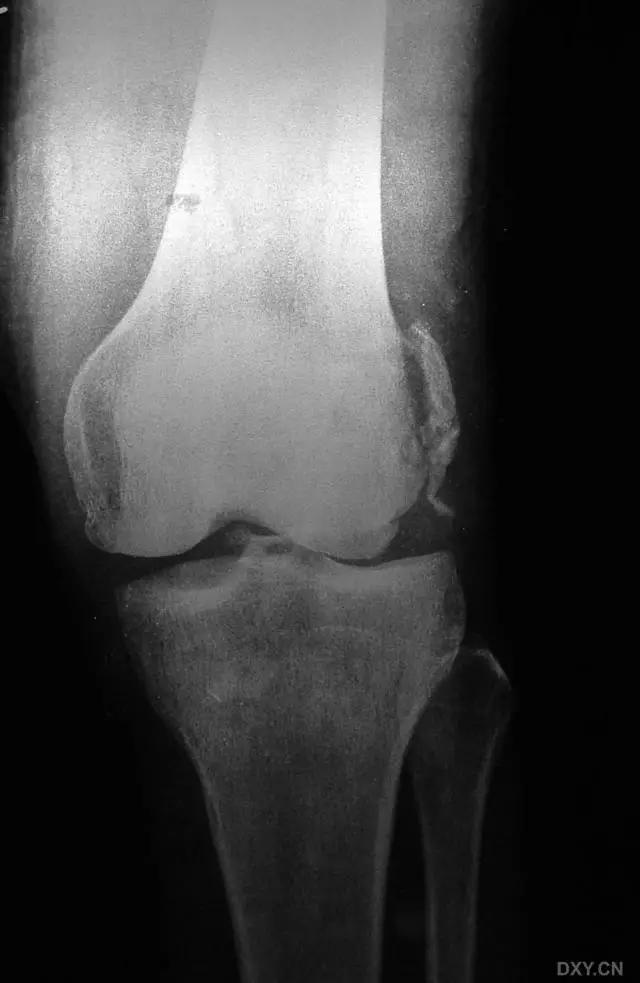

8. Segond 骨折和反向 Segond 骨折

(1)Segond 骨折

是发生在胫骨平台外侧的垂直撕脱性骨折。这种骨折在前后位 X 线片上显示最佳。屈曲位时膝关节受到内旋*力暴**作用,导致皮质骨撕脱性骨折,这种骨折常发生在运动员身上。

常引起股骨内髁和胫骨平台后内侧骨挫伤,75%~100% 的患者伴前交叉韧带断裂,33% 的患者伴外侧半月板损伤。

一位足球运动员的 Segond 骨折。A 正位片示关节线下方胫骨外侧皮质撕脱(箭头)。B MRI 冠状位 T1 加权像示附着于髂胫带的骨折碎片(空箭头)(来源:Radiol Clin N Am 53 (2015) 737–755,YU,Ohio)

(2)反向 Segond 骨折

胫骨平台内侧皮质骨撕脱性骨折,被称为内侧 Segond 骨折或反向 Segond 骨折。这种骨折的旋转机制与 Segond 骨折相反,该骨折与后交叉韧带断裂及内侧半月板损伤相关。

一位足球运动员的反向 Segond 骨折。A 正位片示关节线处的胫骨内侧见一细小骨折片(箭头)。B MRI 冠状位 T1 加权像示骨折片出现在内侧副韧带关节囊附着处(方框)(来源:Radiol Clin N Am 53 (2015) 737–755,YU,Ohio)